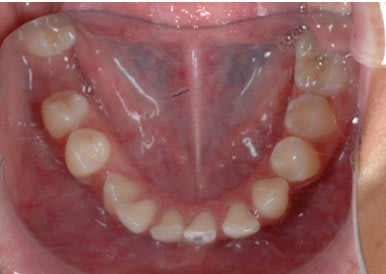

SI joint les photo intra buccal pre traitement et pendant traitement.

Comment expliquer vous le développement ce canting en frontal et de l'open bite en Postérieur ?

Qu'elle est la source du mal ?